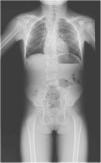

The plain radiograph (Fig. 1) and magnetic resonance imaging (Fig. 2) of the spine evinced abnormalities, and the next generation sequencing skeletal dysplasia panel (463 genes) identified a compound heterozygous variant, NM_016941.3:c.[988G>T];[1312T>C], p.[(Gly330Cys)];[(Cys438Arg)], in the DLL3 gene. Each parent carried one of the alternate alleles. Both were classified as variants of uncertain significance by the American College of Medical Geneticists.

Jarcho-Levin syndrome, also known as spondylocostal dysostosis (OMIM #277300) is an autosomal recessive genetic disease characterized by segmentation defects of the vertebrae.1,2 It should be suspected in individuals presenting with short stature, short neck and trunk asymmetries and is confirmed in imaging tests by the presence of anomalies such as hemivertebrae, block fusion or rib deformities. The results of genetic testing suggested that the identified changes in DLL3 could be the cause of dysplasia, but did not allow confirmation of the diagnosis, as they were variants of uncertain significance. The management consists of supportive care, and infection is the most frequent complication.3